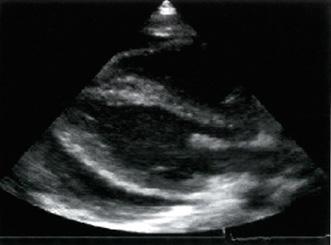

Ecocardiograma

Confirma el derrame pericárdico (efusión > 50 ml).

Espacio anecoico entre el pericardio y el epicardio evalúa el volumen.

<10 mm: pequeño (300 ml)

10-20 mm: moderado (500 ml) > 20 mm: severo (> 700 ml)